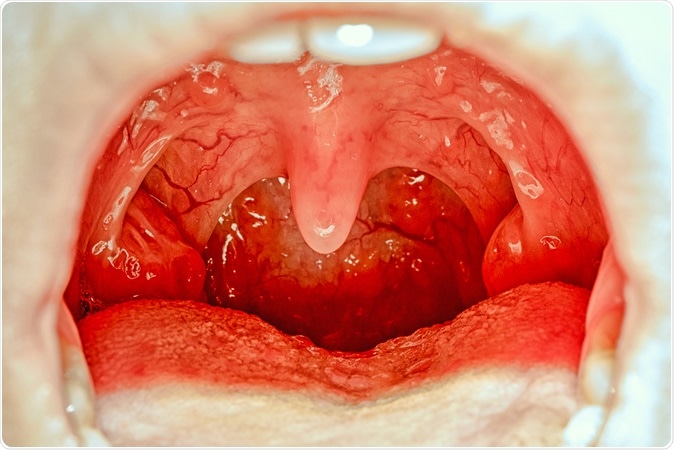

Open mouth showing tonsils. Image Credit: Elena11 / Shutterstock